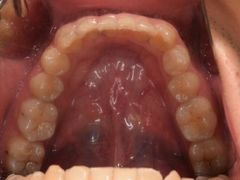

• -德伦口腔

宣有爱 | 19-05-25

报错